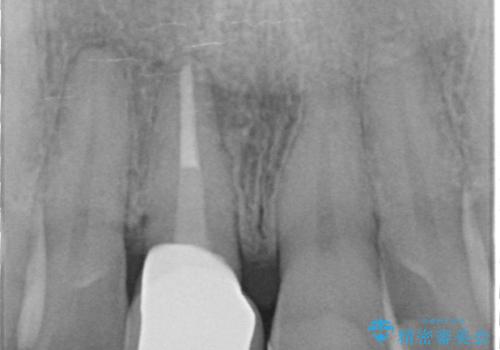

- 3週間後に迫った結婚式までになんとか前歯をきれいにしたいという希望で来院されました。

一回の治療時間を長く取り、限られた時間で最大限の結果を出せるよう集中治療を計画します。

ただ見えるクラウンを白くきれいにするのではなく、長期的な歯の予後を考えると根管治療・ファイバーコア築盛・精密な歯牙形成等クリアすべき条件は多々あると言えます。